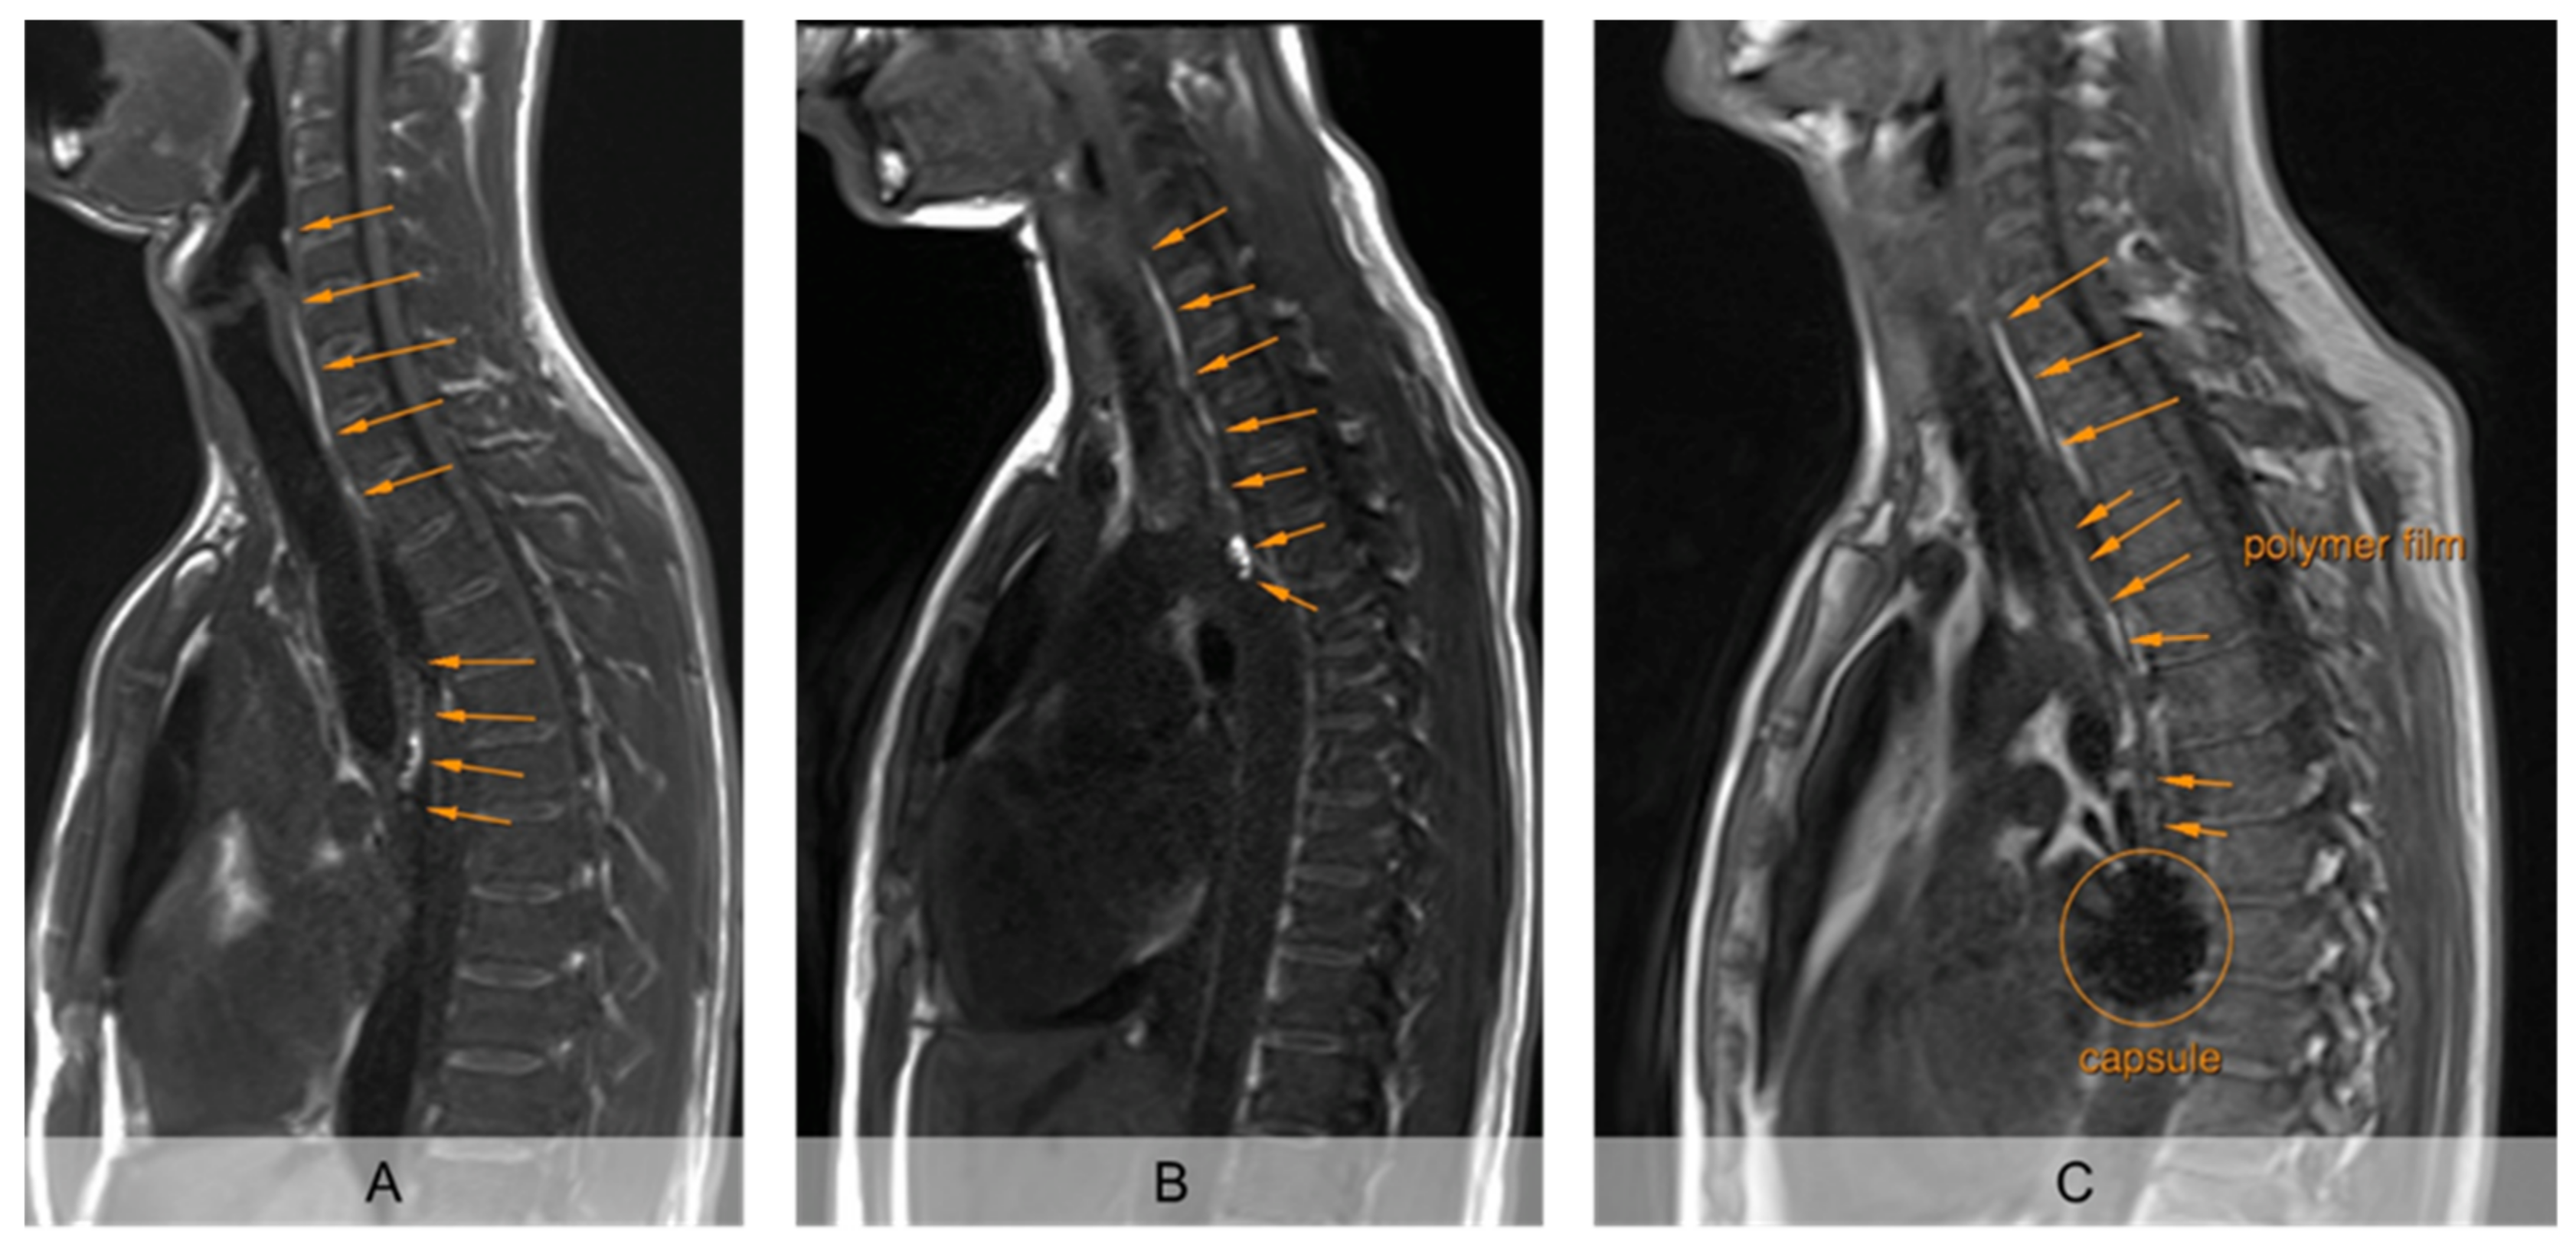

The unrolled PVA film in the esophagus was clearly detectable from the first recording 2 min after intake in strongly T1 weighted MRI, so that its unrolled length was measurable (Figure 2). The mucoadhesive PVA film contrasted by hibiscus tea was clearly visible from the surrounding tissue in all subjects on all days. Moreover, the sinker loaded with iron oxide used in setup B showed a clear signal extinction on MRI, so that the fate of the carrier capsule could also be evaluated (Figure 2C).

Figure 2.

Exemplary representation of sagittal imaging 5 min after application of the EsoCap system. (A): (Almost) completely unrolled film (study setup A, without additional sinker). (B): Incompletely unrolled film, with particularly intense signal of the unrolled film in the capsule (study setup A, without additional sinker). (C): (Nearly) completely unrolled film, using sinker, loaded with iron oxide for signal extinction (study setup B).